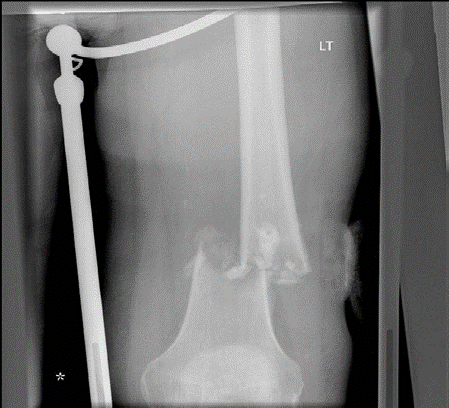

Lower limb Trauma Structured oral examination question 2 A 79-year-old woman fell in her garden sustaining th…